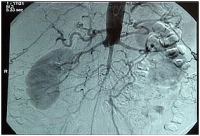

Filmbeispiel:

Hoher Aortenverschluss bei subtotaler Iliakalgabelstenose, Verschluss der A. iliaca communis re. und Thrombosierung im Bereich der A. iliaca externa li. (klinisch PAVK IIb bds.)

-> TASC D, somit Empfehlung zur offenen Rekonstruktion

Präoperative i.a. DSA

Hoher Aortenverschluss bei Bifurkationsstenose

Verschluss der A.iliaca communis beidseits, links Embolus in der A. iliaca externa